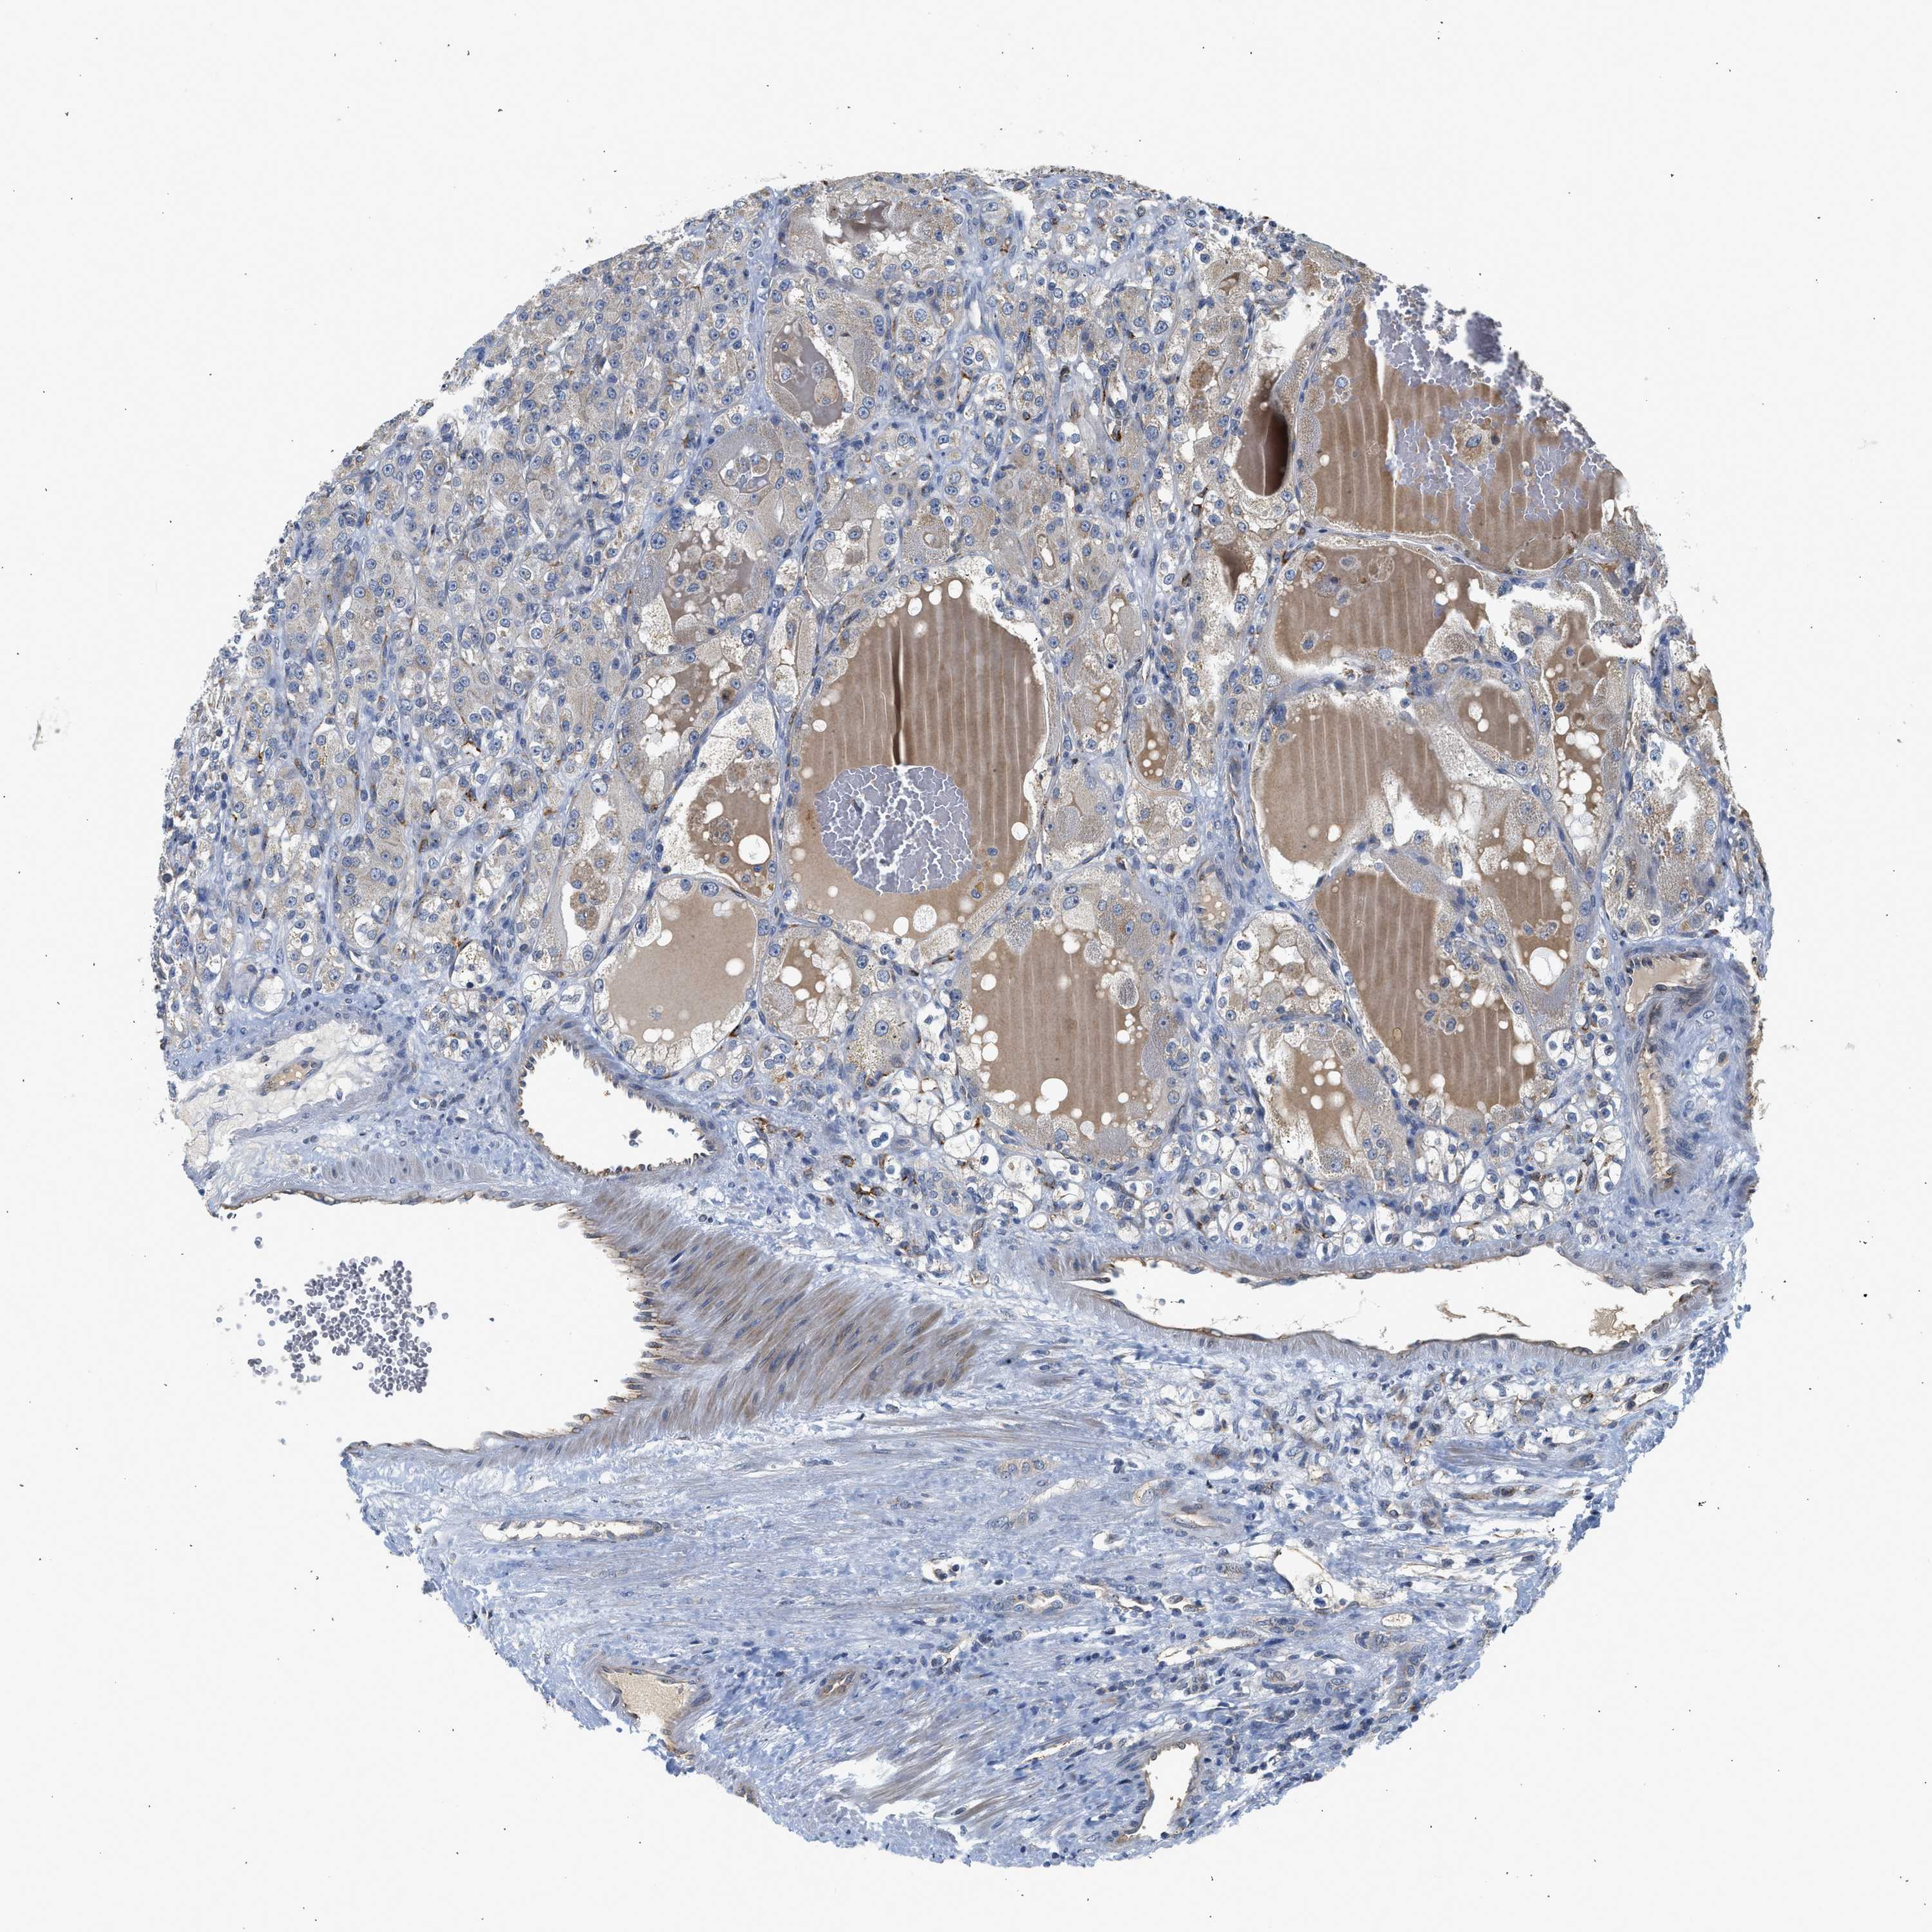

KIDNEY CHROMOPHOBE (TCGA) - Interactive survival scatter ploti

The Survival Scatter plot shows the clinical status (i.e. dead or alive) for all individuals in the patient cohort, based on the same data that underlies the corresponding Kaplan-Meier plots. Patients that are alive at last time for follow-up are shown in blue and patients who have died during the study are shown in red.

The x-axis shows the expression levels (FPKM) of the investigated gene in the tumor tissue at the time of diagnosis. The y-axis shows the follow-up time after diagnosis (years). Both axes are complimented with kernel density curves demonstrating the data density over the axes. The top density plot shows the expression levels (FPKM) distribution among dead (red) and alive patients (blue). The right density plot shows the data density of the survived years of dead patients with high and low expression levels respectively, stratified using the cutoff indicated by the vertical dashed line through the Survival Scatter plot. This cutoff is automatically defined based on the FPKM cutoff that minimizes the p-score. The cutoff can be changed by dragging the vertical line or by entering a cutoff value in the square labeled "Current cut-off".

Under the Survival Scatter plot the p-score landscape (black curve; left axis) is shown together with dead median separation (red curve; right axis). Dead median separation is the difference in median mRNA expression between patients who have died with high and low expression, respectively. It is calculated as follows: median FPKM expression of dead patients with high expression - median FPKM expression of dead patients with low expression. This is intended to aid the user in visually exploring custom cutoffs and the associated p-scores and dead median separation.

Individual patient data is displayed and can be filtered by clicking on one or more of the category buttons on the top of the page. Categories describing expression level and patient information include: high, low, alive, dead, female, male and tumor stages. The scale of the x-axis can be toggled between linear and log-scale by clicking on the "x log" button. Mouse-over function shows TCGA ID, patient information and mRNA expression (FPKM) for each patient.

& Survival analysisi

Kaplan-Meier plots summarize results from analysis of correlation between mRNA expression level and patient survival. Patients were divided based on level of expression into one of the two groups "low" (under cut off) or "high" (over cut off). X-axis shows time for survival (years) and y-axis shows the probability of survival, where 1.0 corresponds to 100 percent.

PIM1 is not prognostic in Kidney Chromophobe (TCGA)

Best expression cut offi

Based on the FPKM value of each gene, patients were classified into two groups and association between prognosis (survival) and gene expression (FPKM) was examined. The best expression cut-off refers the FPKM value that yields maximal difference with regard to survival between the two groups at the lowest log-rank P-value. Best expression cut-off was selected based on survival analysis .

When clicking on this number, the vertical dashed line indicating cut-off, the interactive survival plot, and the Kaplan-Meier curve will be adjusted to show results based on the best expression cut-off.

: 47.71

Median expressioni

Median expression refers to the median FPKM value calculated based on the gene expression (FPKM) data from all patients in this dataset. When clicking on this number, the vertical dashed line indicating cut-off, the interactive survival plot, and the Kaplan-Meier curve will be adjusted to show results based on the median expression.

: N/A

Median follow up timei

Median follow up time refers to the median time (years) after diagnosis with this type of cancer, based on clinical data from all patients in this dataset.

P scorei

Log-rank P value for Kaplan-Meier plot showing results from analysis of correlation between mRNA expression level and patient survival.

N/A

5-year survival highi

5-year survival for patients with higher expression than the expression cutoff.

For melanoma and glioma, 3-year survival is shown.

5-year survival lowi

5-year survival for patients with lower expression than the expression cutoff.

TCGA RNA samplesi

RNA-seq data is reported as average FPKM (number Fragments Per Kilobase of exon per Million reads), generated by the The Cancer Genome Atlas (TCGA) .

Normal distribution across the dataset is visualized with box plots, shown as median and 25th and 75th percentiles. Points are displayed as outliers if they are above or below 1.5 times the interquartile range. FPKM values of the individual samples are presented next to the box plot.

Average pTPM 59.7

Number of samples 64